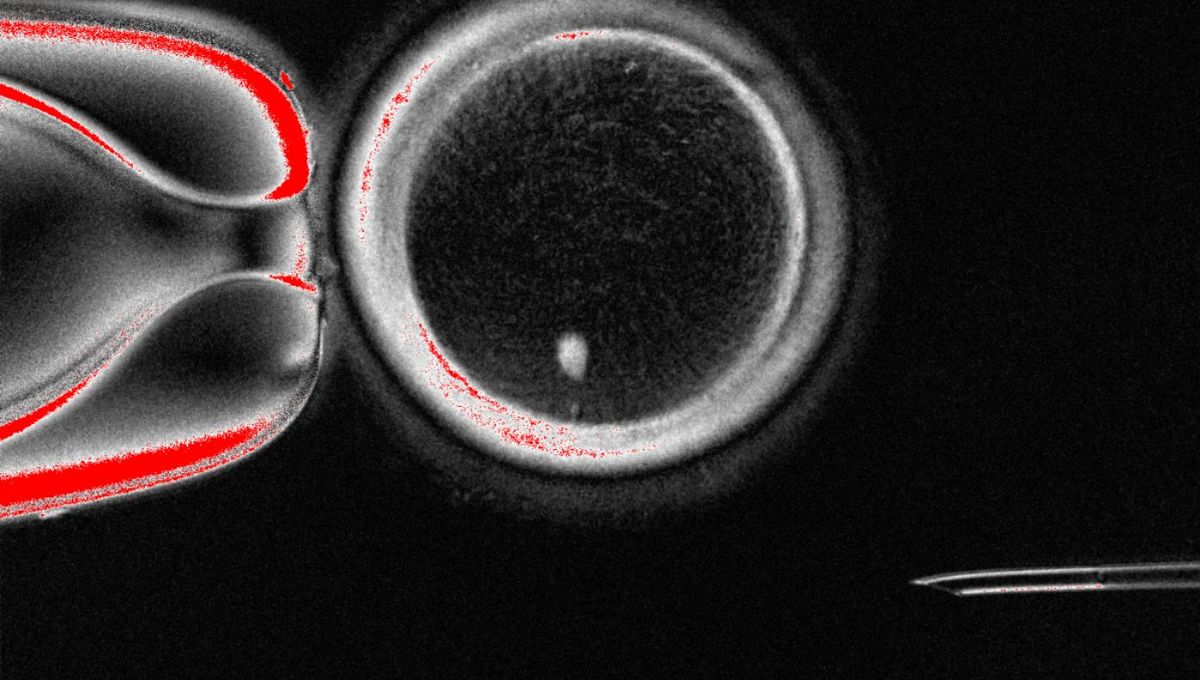

In the new study, led by researchers at Oregon Health & Science University, the nuclei from skin cells were inserted into donor eggs that had had their nuclei removed. The team then induced the egg cells to undergo a process they’ve called “mitomeiosis”. Although similar to mitosis – the process of natural cell division that results in two identical copies of a parent cell – mitomeiosis has key differences that result in one set of chromosomes being discarded, so the resultant daughter cell is haploid (containing only 23 chromosomes).

In total, the scientists were able to generate 82 functional egg cells from this process, which they then fertilized with sperm in the lab. Of these, around 9 percent developed into blastocysts, an early stage of embryonic development, after six days. Culturing was not continued after this point as this is when transfer into the uterus would happen during typical IVF.